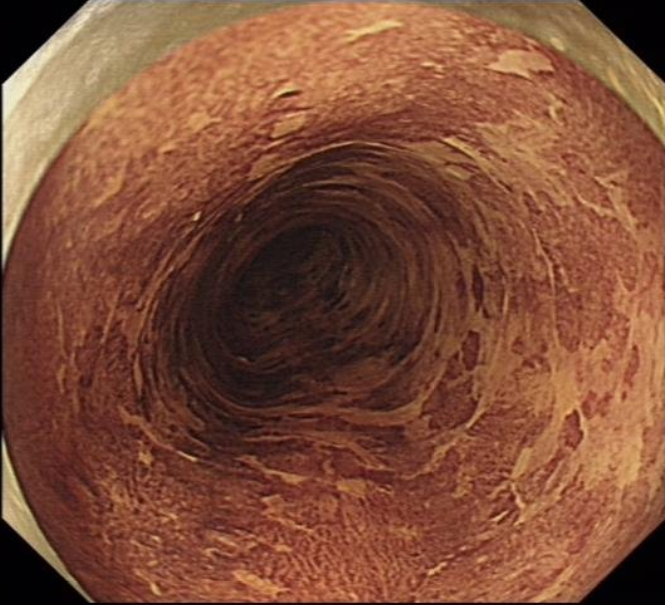

男 年龄:53岁 来源:门诊 检查类型: 无痛胃镜 检查所见:食管距

来源:门诊 检查类型:无痛胃镜 检查所见:食管距门齿30cm至scj见黏膜

性别:男 年龄:74岁 来源:门诊 检查类型:无痛胃镜 检查所见:食管